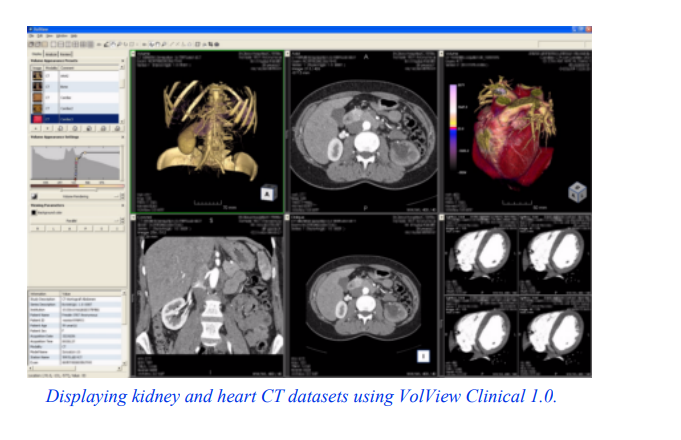

12.1三维医学成像

放射学是一门处理人体解剖图像的医学学科。这些图像来自各种医学成像设备,包括x射线、x射线计算机断层扫描(CT)、

磁共振成像(MRI)和超声波。每种成像技术,称为一次成像

图12-1人脑CT切片。

情态,有特殊的诊断优势。方式的选择是放射科医生和转诊医生的工作。在大多数情况下,放射科医生处理二维图像,但在某些情况下,三维模型可以帮助放射科医生进行诊断。放射科医生接受过特殊的训练来解释二维图像,并理解这些二维图像中复杂的解剖关系。然而,在与转诊医生和外科医生打交道时,放射科医生有时难以沟通这些关系。毕竟,外科医生在计划和执行手术时是三维的;此外,他们更容易观察和使用三维模型。

本案例研究涉及CT数据。计算机断层扫描测量x射线穿过人体时的衰减。CT图像由灰色级别组成,从黑色(空气)到灰色(软组织),再到白色(骨骼)。图12 - 1为头部CT横切面。这个切片是垂直于脊柱的,大约穿过耳朵的中部。头部周围的灰色边界清楚地显示出耳朵和鼻梁。切片内部的深色区域是鼻道和耳道。亮的部分是骨头。这项研究包含93个这样的切片,间隔1.5 mm。每个切片有2562像素,间隔0.8毫米,12位灰度。

我们面临的挑战是将这些灰色数据(超过12兆字节)转换为有助于外科医生的信息。幸运的是,我们的可视化工具包有合适的技术。我们将使用等轮廓技术来提取皮肤和骨骼表面,并显示正交横截面,以将等值面放在上下文中。根据经验,我们知道密度值500将定义空气/皮肤边界,值1150将定义软组织/骨骼边界。

在VTK术语中,医学成像切片数据是图像数据。回顾第5章,对于图像数据,数据的拓扑和几何结构是隐式已知的,只需要维度、原点和数据间距。

我们在这个案例研究中所遵循的步骤在许多三维医学研究中是常见的。

1. 读取输入。

2. 对于每个感兴趣的解剖特征,创建一个等值面。

3.将模型从病人空间转换到世界空间。

4. 渲染模型。

本案例详细描述了如何使用等轮廓法读取输入数据并提取解剖特征。正交平面将显示使用基于纹理的技术。在此过程中,我们还将向您展示如何呈现数据。最后简要讨论一下医疗数据转换。本节所示示例的完整源代码可从Medical1获得。cxx,医疗2。cxx和Medical3。cxx。